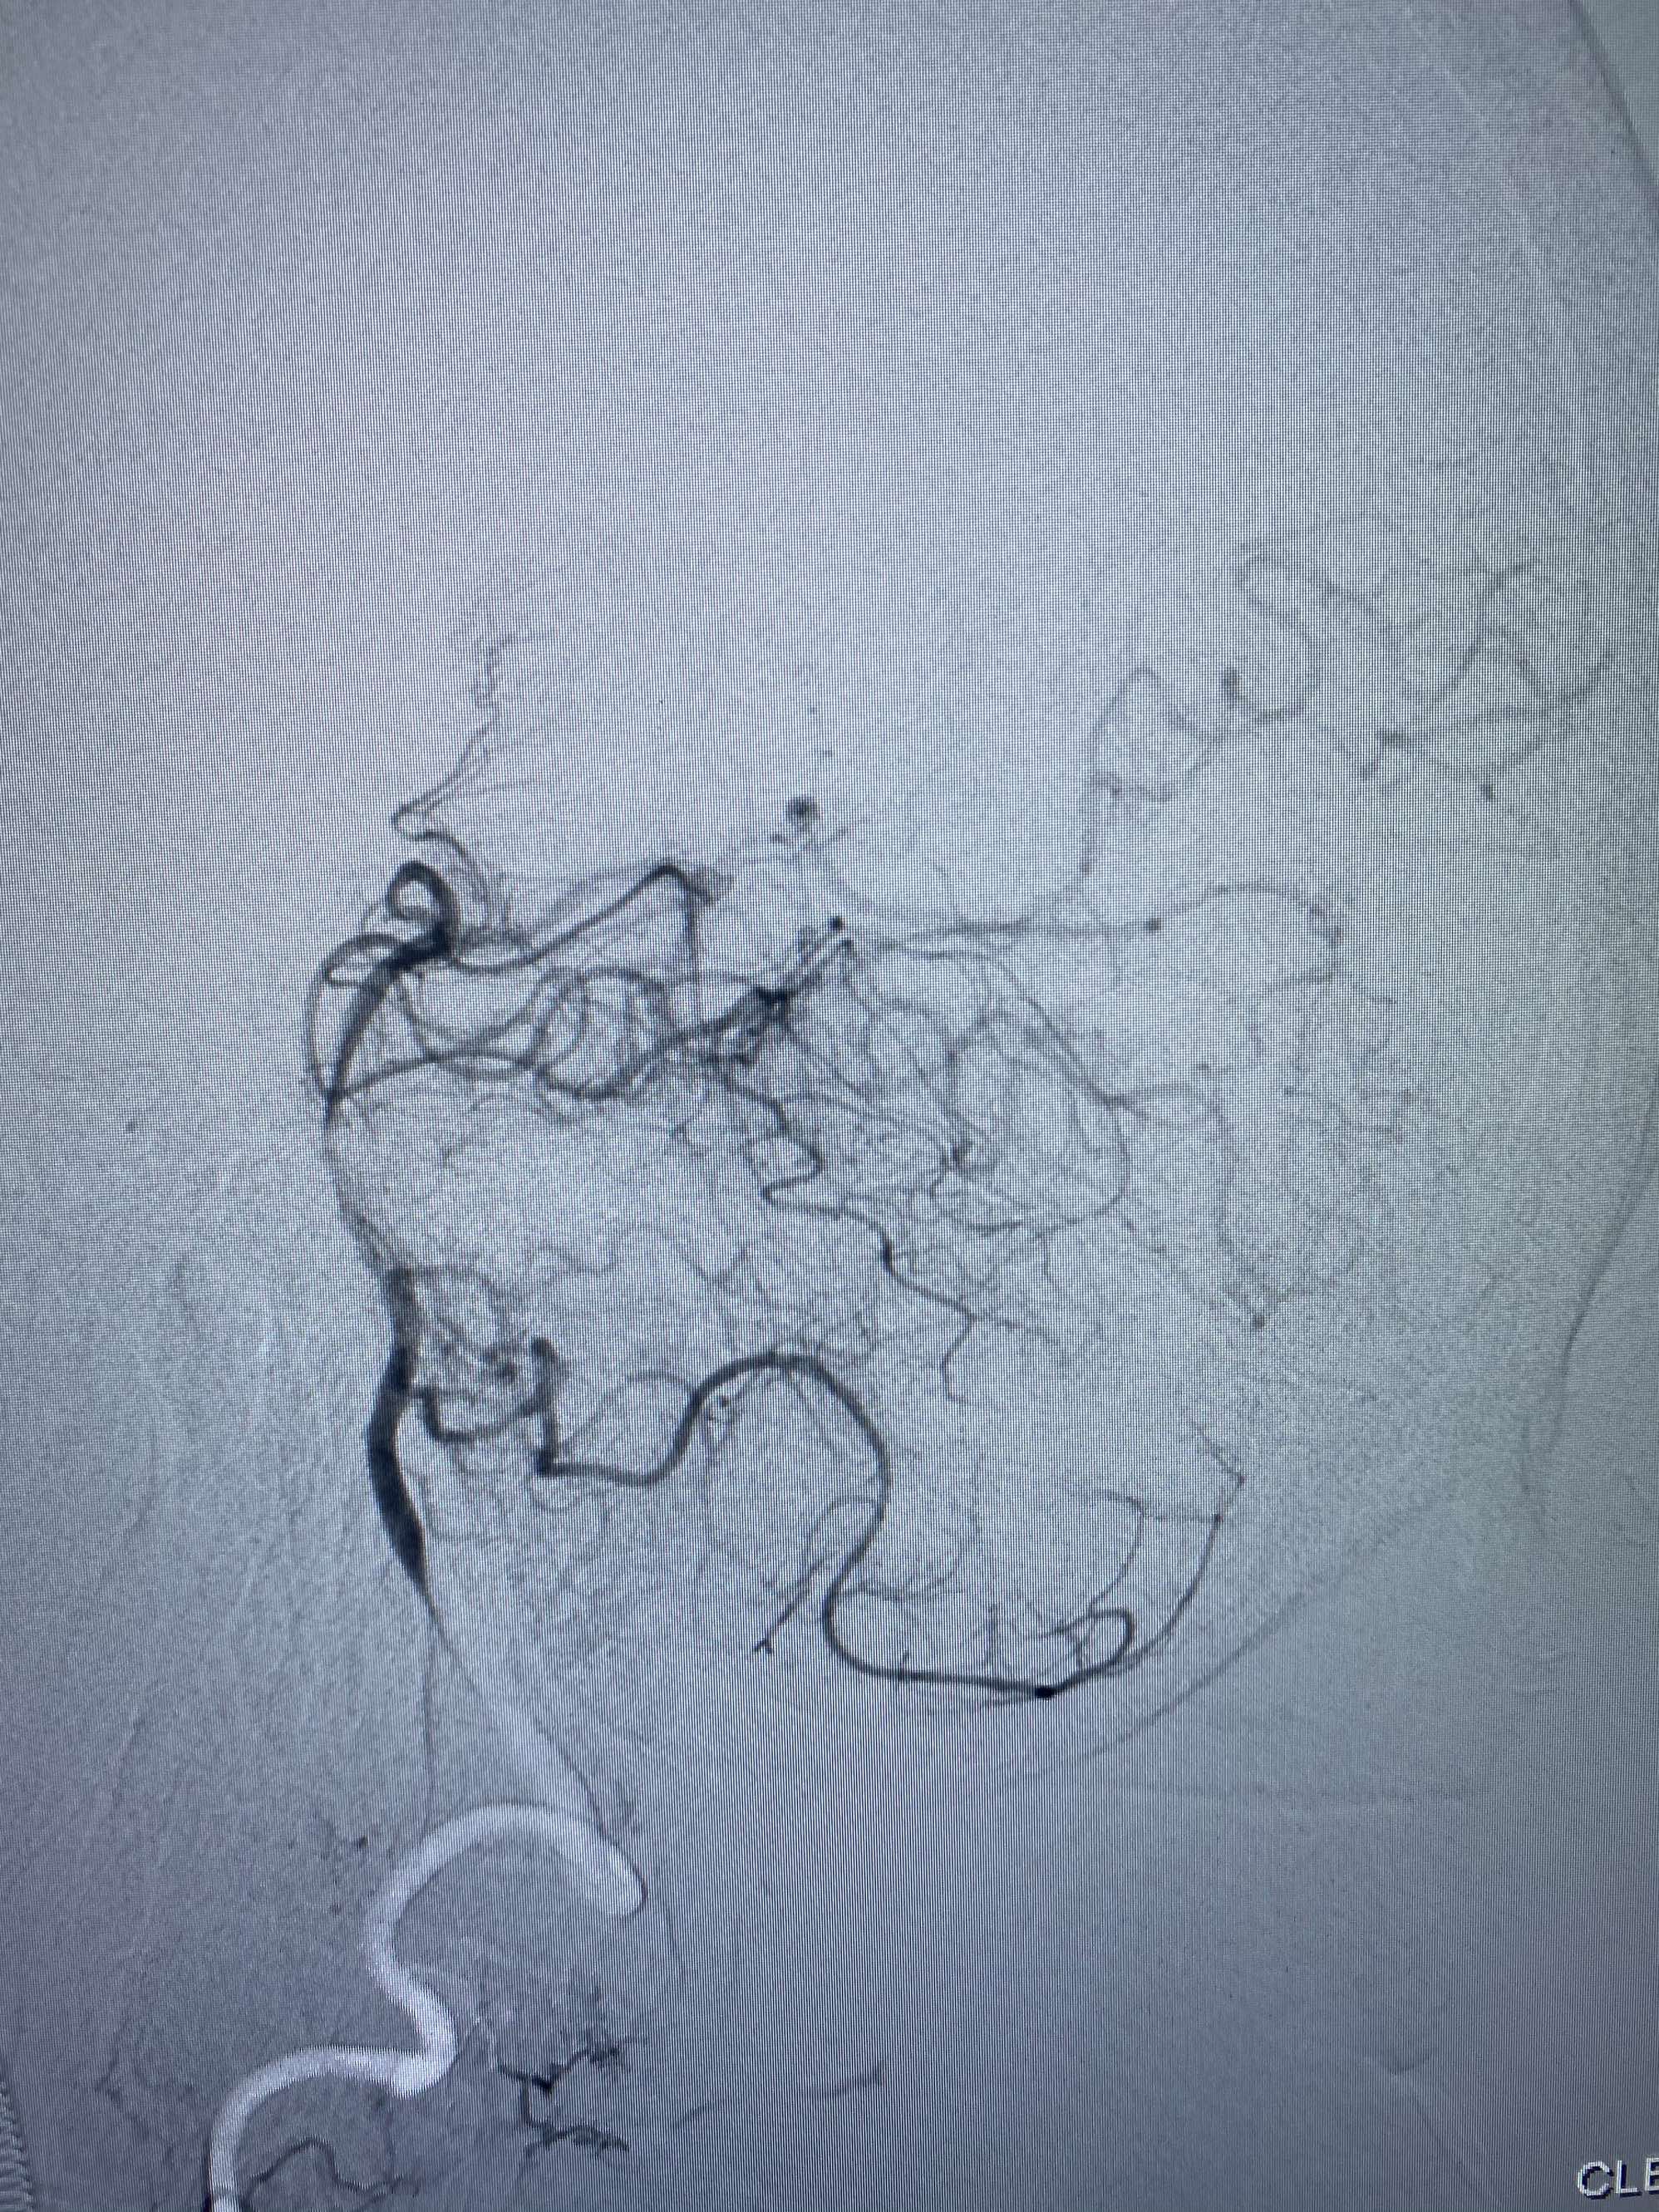

MLS,M79Y,sah,双侧MCA烟雾病,Heubner返动脉瘤,前交通段开窗,细支发出Heubner返动脉,瘤颈细长,瘤颈口比微导管细,弹簧圈2mmx3cm“隔山打牛”填塞治愈,Heubner返动脉保留。